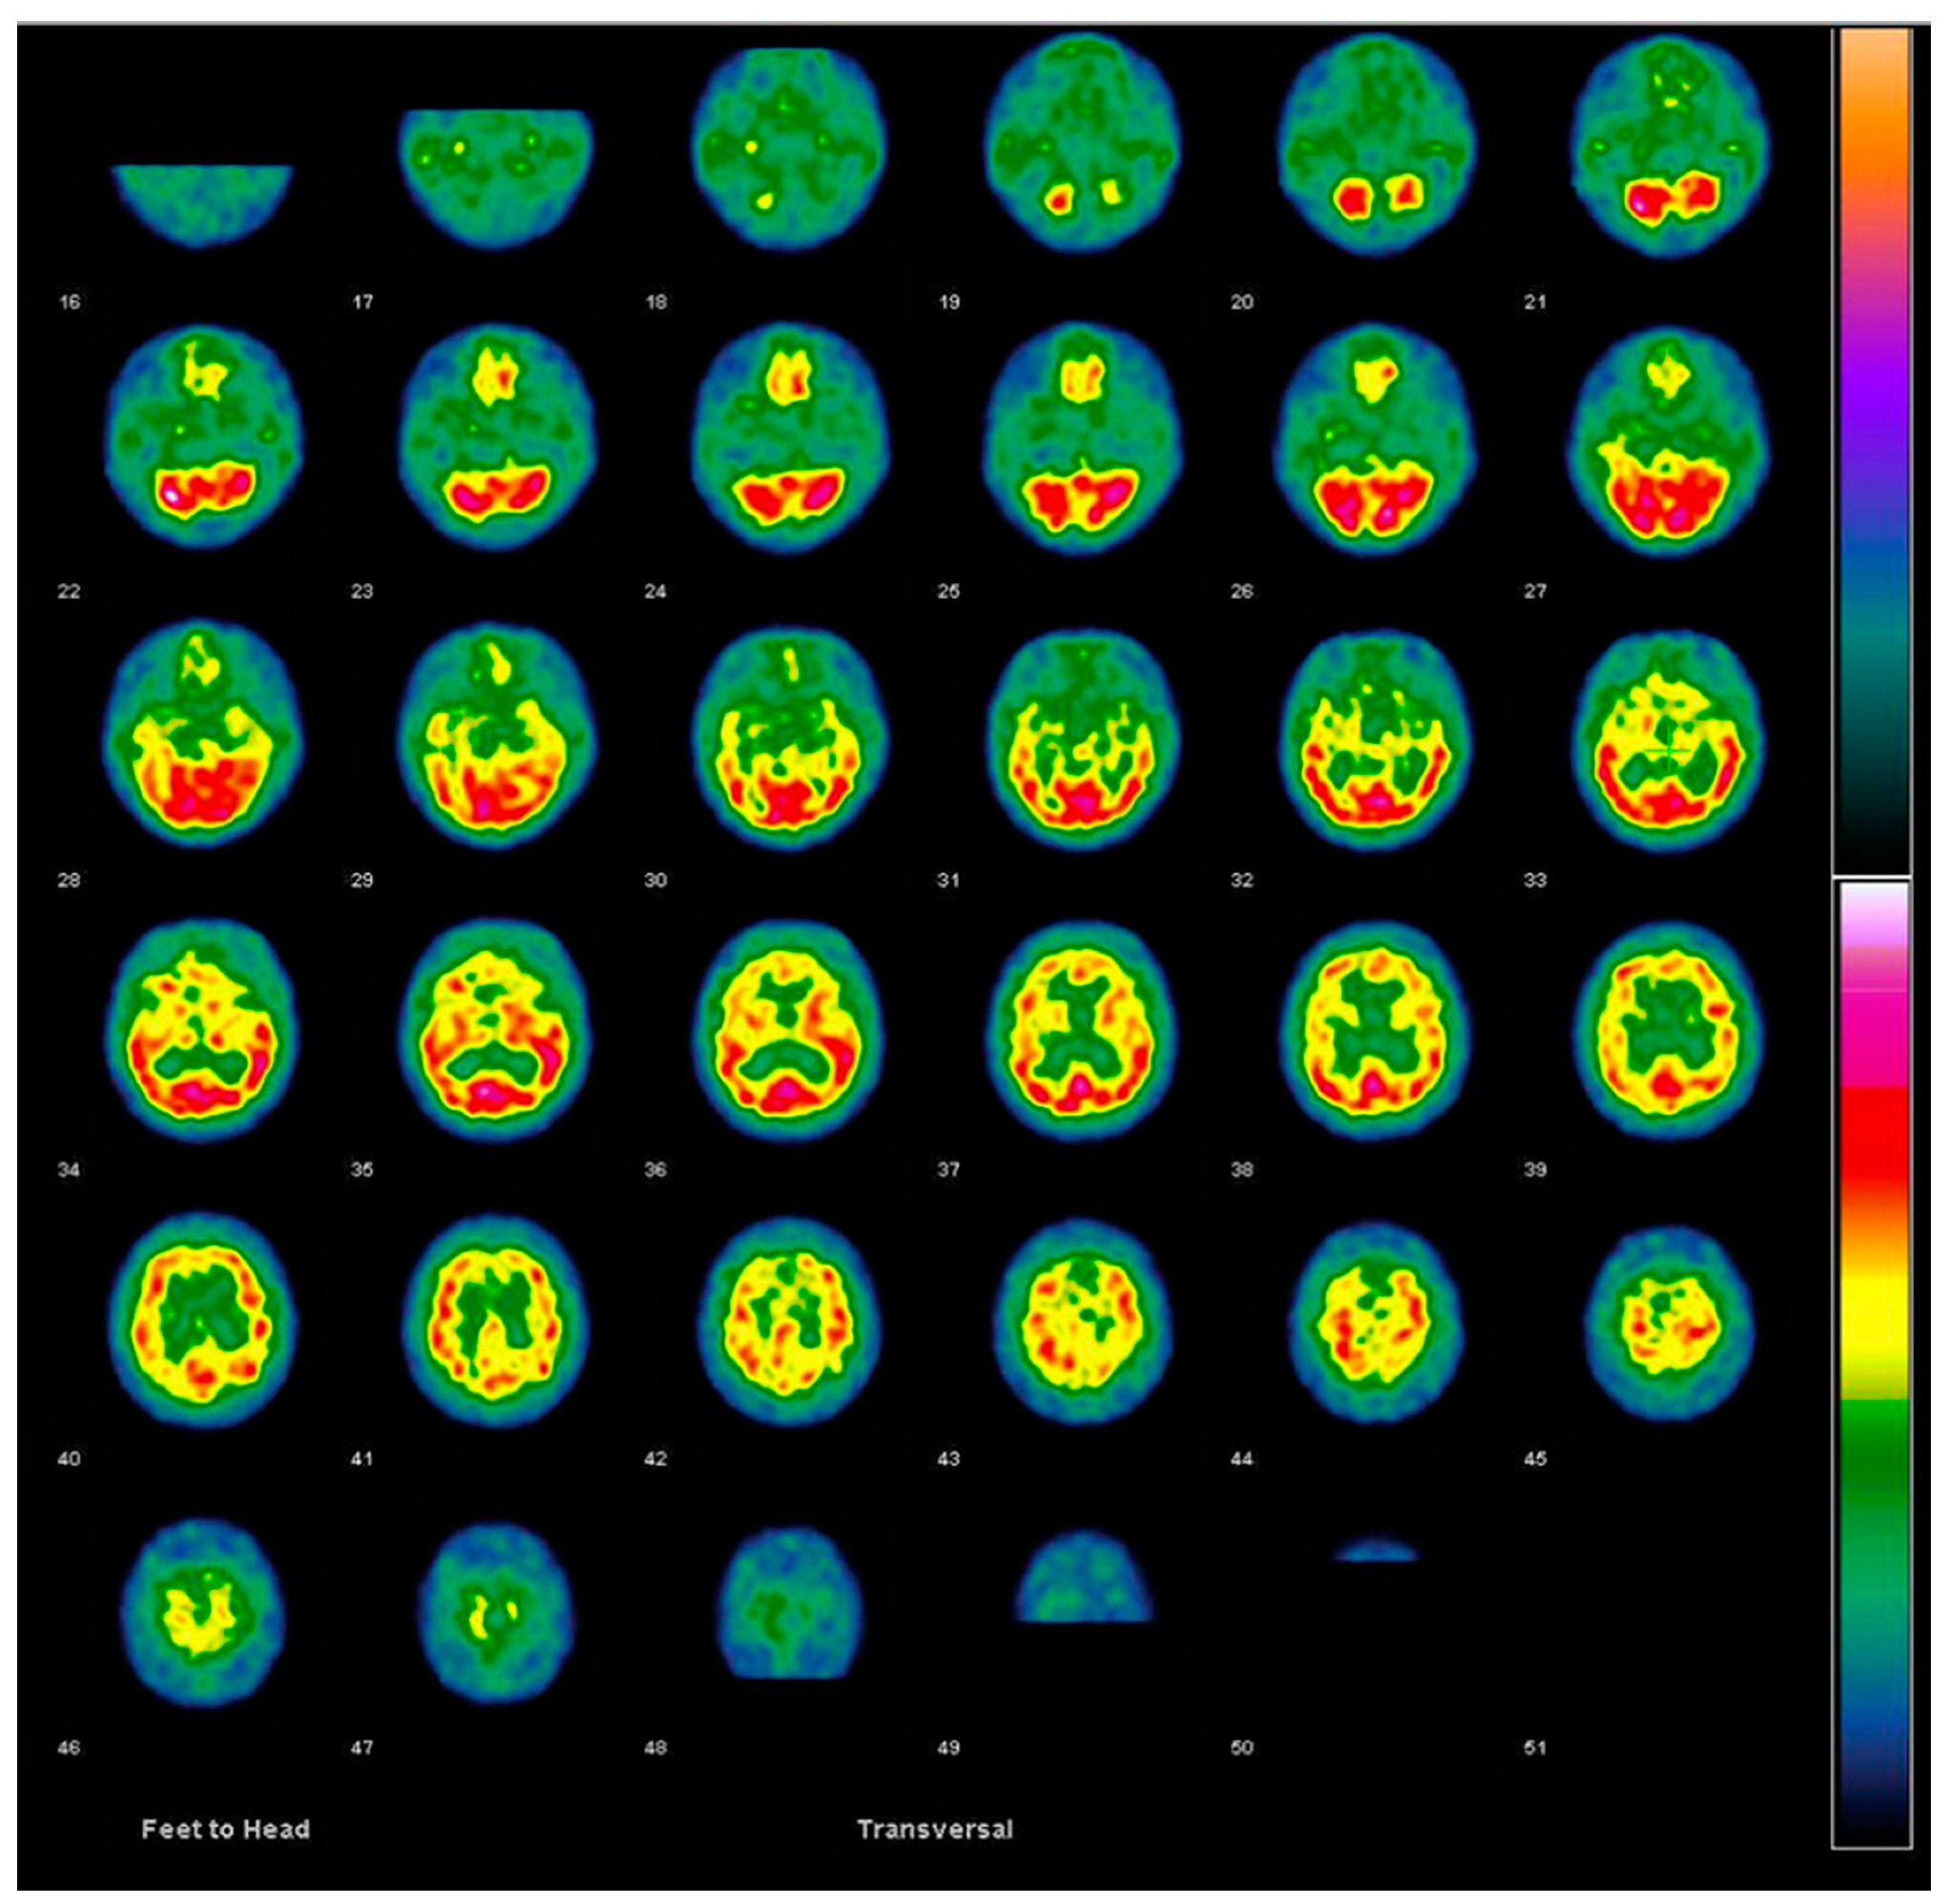

6.1. Brain Perfusion SPECT and FDG PET

6.1.1. Imaging Data Display [45,50]

| Dementia Type | Hypoperfusion/Metabolic Cortical and Subcortical Regions | Preservation of Perfusion/Metabolism |

|---|---|---|

| Alzheimer’s disease (AD) |

|

| Dementia with Lewy bodies (DLB) |

| Frontotemporal lobar degeneration (FTLD) |

| Vascular dementia |